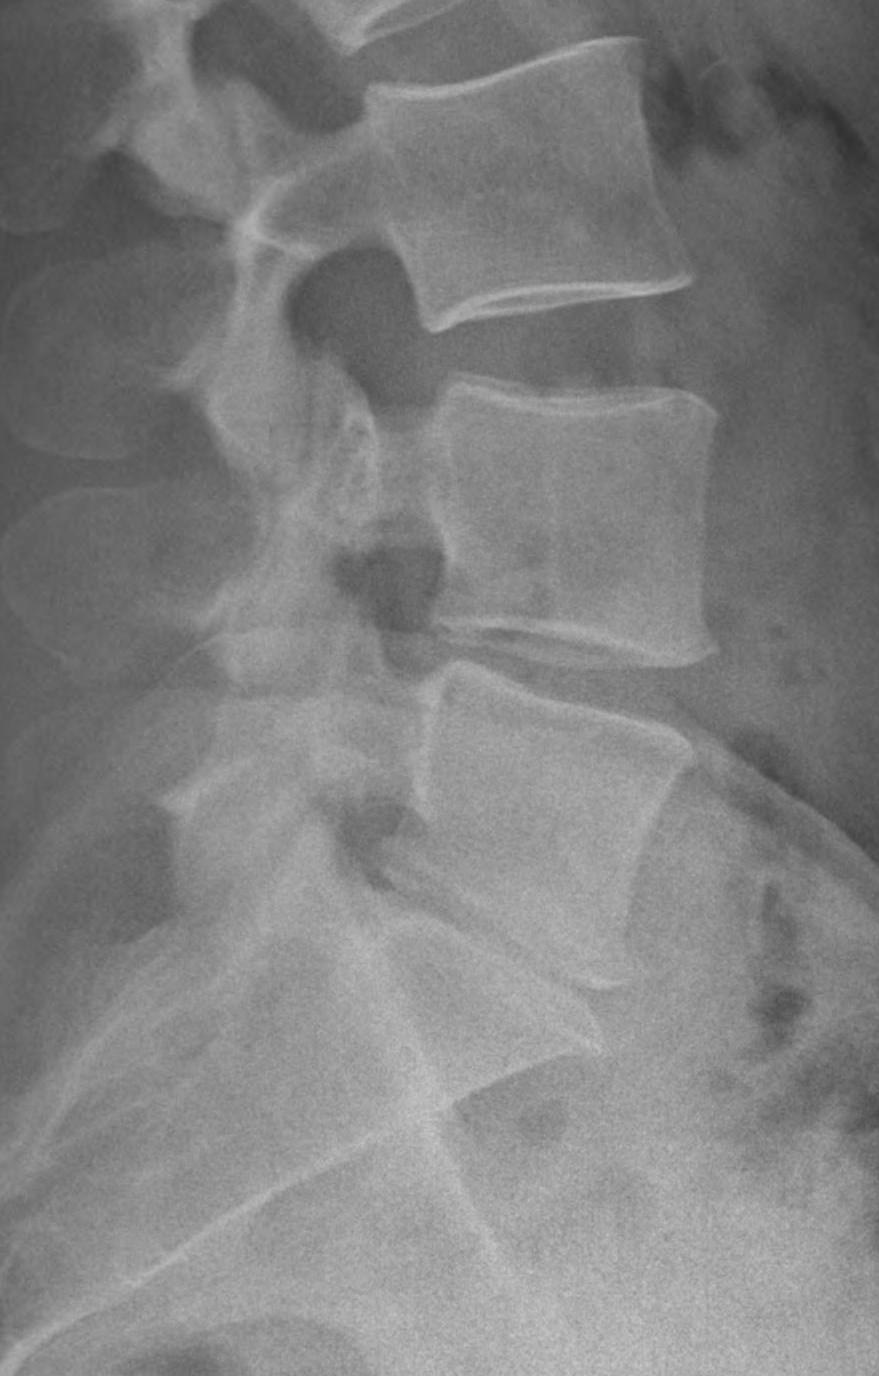

La diagnosi strumentale della discopatia degenerativa viene comunemente posta con esame RNM (figg.3-4), ed in fase avanzata anche con una semplice radiografia in proiezione laterale (fig.5),standard o dinamica (figg.6-7). La discografia può essere utile in alcune circostanze.

• Figura 05